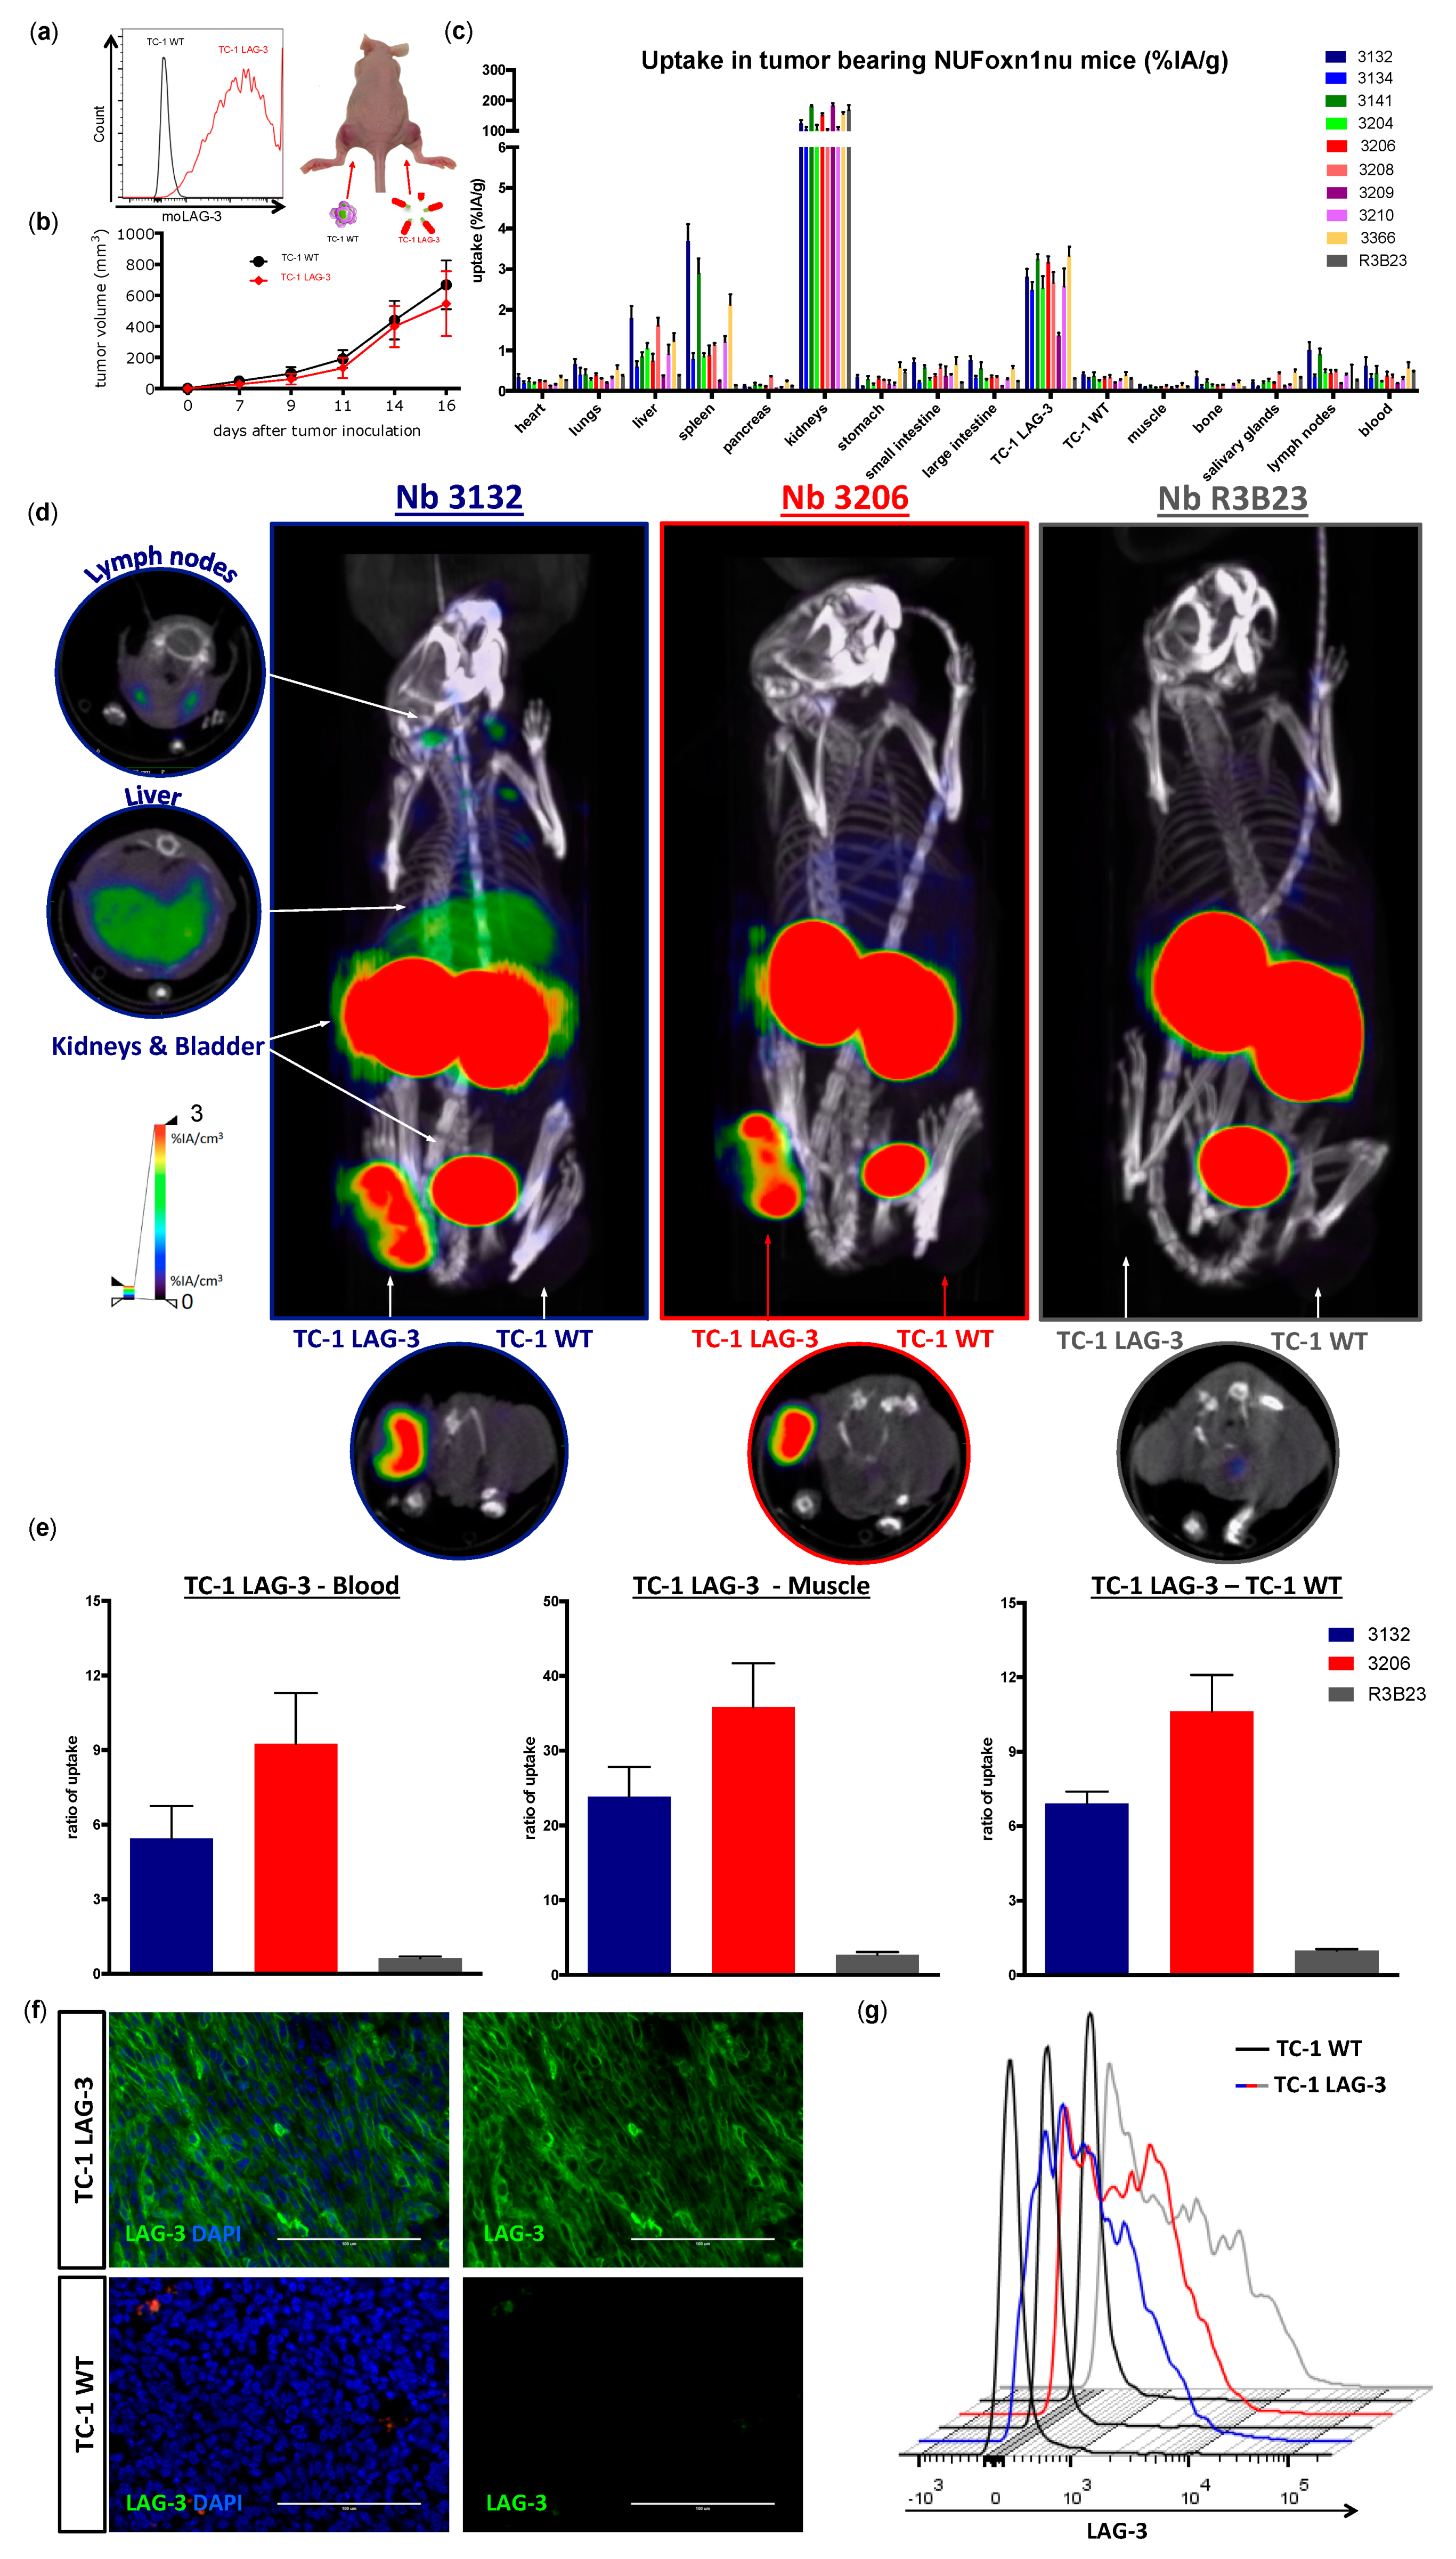

Next, we evaluated the potential of the

99mTc-labeled Nbs to detect moLAG-3 present in dense tissues like tumors. For this purpose, we used an artificial model where mice, harboring a subcutaneous tumor that was lentivirally modified to overexpress moLAG-3, are imaged using our

99mTc-labeled Nbs. Moreover, athymic nude mice were used for these experiments in order to prevent rejection of the lentiviral transformed TC-1 tumors. The uptake of Nb 3132 and 3206 in the moLAG-3 expressing tumors was comparable and with high contrast levels as fast as 1 h after injection. This shows that Nbs are excellent candidate molecules for the visualization of immune checkpoints within the tumor environment, like previously described in Broos et al. using PD-L1 targeting Nbs [

31]. Moreover, in view of repeated imaging, which could be interesting for follow up of the immune checkpoint status during therapy, it is important to note that Nbs are weakly immunogenic because of their high similarity with human variable heavy chain fragments properties (reviewed by [